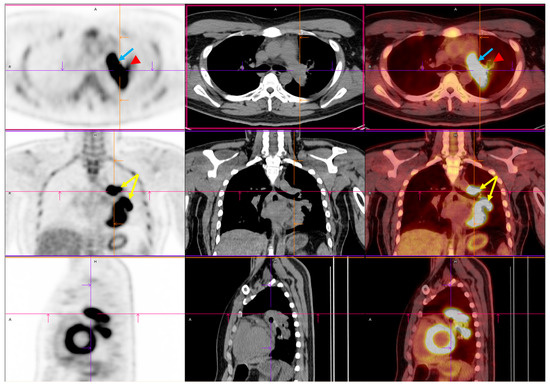

Figure 2. Preoperative PET/CT imaging. FDG PET/CT imaging demonstrated intense FDG uptake involving the left upper and lower lobes within the centrally located mass (yellow arrow) [4,5,6]. Upon initial imaging, the primary lesion exhibited a maximum standardized uptake value (SUVmax) of 14.52, with a delayed SUVmax of 21.08. This indicated significant metabolic activity and a high tumor glycolytic rate. The lesion’s metabolic borders corresponded closely to the soft tissue margins observed on CT, confirming its structural and functional malignancy. Crucially, increased FDG uptake was also identified within the left pulmonary artery (blue arrow) (SUVmax: 12.69), where a lobulated intraluminal filling defect had previously been observed on contrast-enhanced CT. The metabolic activity of the intravascular component mirrored that of the adjacent tumor, further supporting the diagnosis of a tumor thrombus rather than a bland thromboembolism [7]. This pattern of contiguous metabolic extension from the primary lung mass into the pulmonary vasculature strongly suggested direct vascular invasion. Mildly increased uptake was noted in the left hilar region (red arrowhead). This raised concerns about potential nodal involvement. Abbreviations: FDG, 18F-fluorodeoxyglucose; PET/CT, positron emission tomography/computed tomography; SUVmax, maximum standardized uptake value.